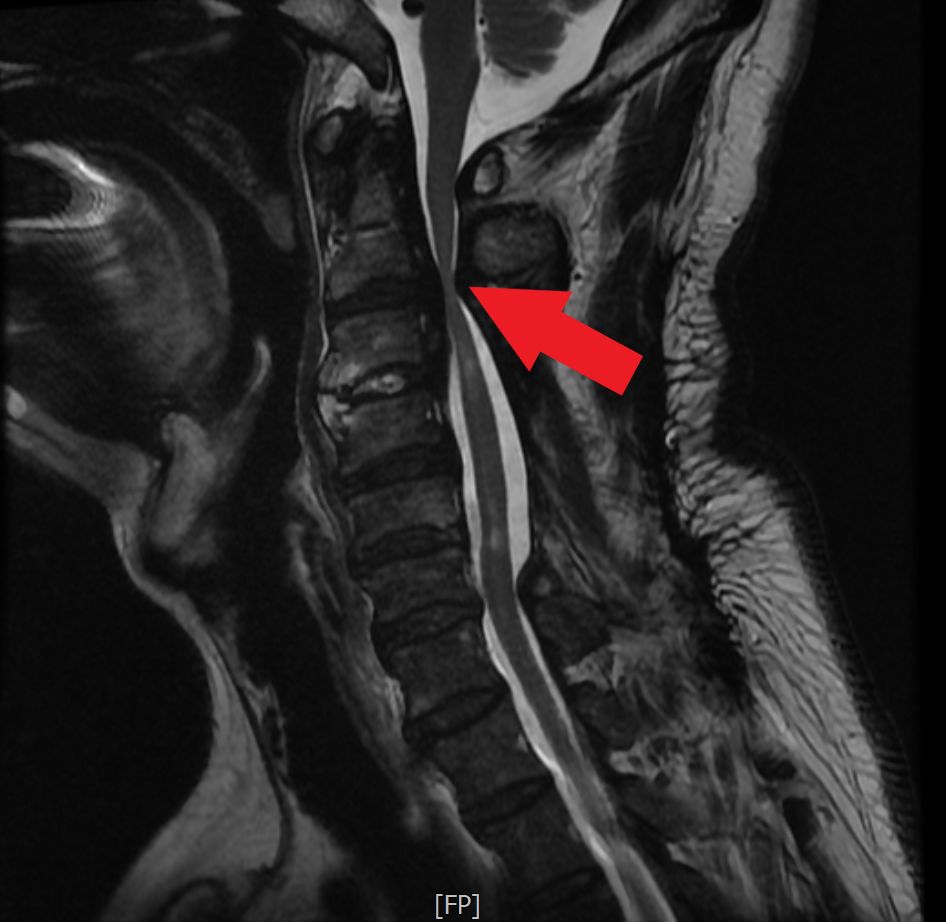

陳先生的頸椎減壓手術確實比較困難,主要是位在第二、三節, 非常高位的後縱韌帶骨化,比一般骨刺還嚴重,已把脊髓神經壓到、 扁到幾乎一條線,洪祥益主任說,脊髓神經比腦神經還要脆弱, 幾乎是可能稍微碰觸就會癱瘓; 一般太嚴重的病人需要從後頸部做大範圍減壓, 但陳先生幾年前已開過後面,開完後第二、三節頸椎反而又更狹窄, 導致後來幾乎是無法走路,站起來就快要跌到的狀態。

洪祥益主任進一步指出,只剩下從頸椎前面做微創手術, 頸椎第二節、三節的位置很高,幾乎從頸椎深入到口腔的高度, 在顯微鏡下,精準地用電鑽把骨刺全部磨乾淨, 再以骨釘固定及骨融合手術; 磨骨刺的過程有點像一塊石頭壓在豆腐上,要以電鑽把石頭磨掉, 風險極高,而執刀醫師必須要很輕巧、不能太用力, 這是最困難的地方,特別是這骨化的韌帶比骨頭還硬, 稍微不慎即可能造成癱瘓, 也因此花蓮慈院神外團隊的脊椎手術全程均有神經監控, 再加上有顯微鏡放大監看,讓手術更安全, 醫師也可較放心的執行術式。

圖:經MRI檢查發現病人的第二、三節頸椎後縱韌帶骨化非常嚴重,受壓迫的神經幾乎扁成一條線。

圖:術前檢查,高位頸椎後縱韌帶骨化,嚴重擠壓脊髓神經。